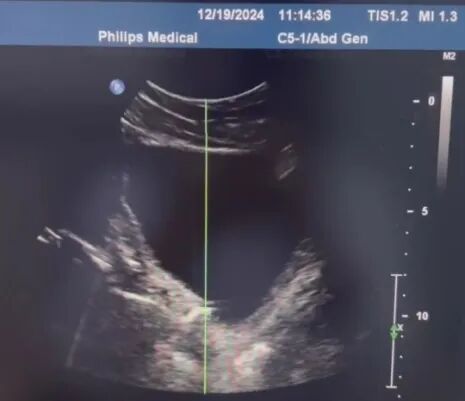

超声定位结石。

2022年10月,烟台山医院启用泌尿碎石中心。在过去两年多的时间里,体外冲击波碎石技术以其无创非侵入性和高效安全性,在治疗泌尿系统结石领域发挥了重要作用,为广大尿路结石患者提供了安全、高效、经济的治疗选择。烟台山医院的体外冲击波碎石治疗系统具备超声、X线双定位功能,兼顾X线阴性以及阳性结石,能够更加清晰、准确评估结石的大小、位置及数量;同时,在治疗实施过程中,可以根据评估结果个体化确定适合的冲击波强度和频率,达到精确高效的碎石效果。治疗持续时间大约为20到30分钟,不需要麻醉,疗程结束后,大多数患者可以立即返回日常生活。这种技术不仅显著降低了治疗风险,缩短了治疗时间,还减少了术后恢复时间,疗程花费少,对患者而言,既减轻了痛苦,又安全、经济、高效。